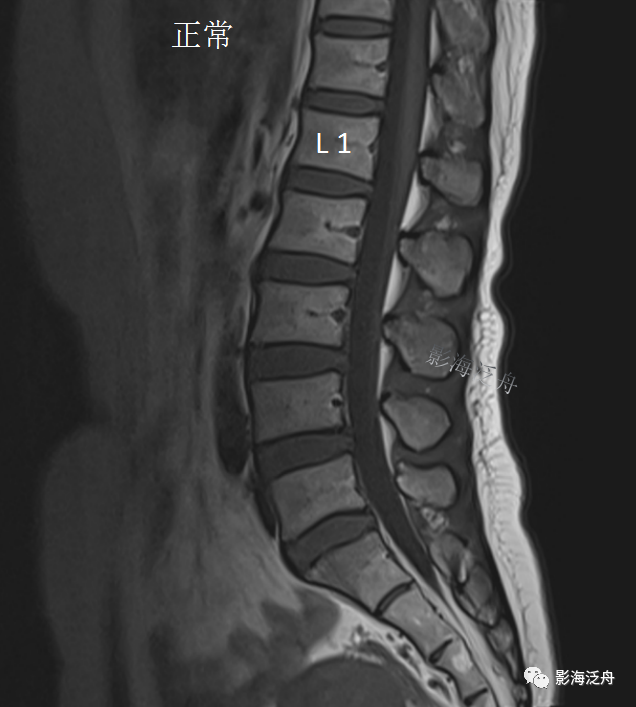

先不着急解开谜底,我们看一个正常片子

看出有什么不一样了吗?